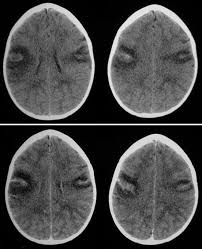

Temporal Lobe Atrophy Post Herpes Simplex Encephalitis Radiology Case Radiopaedia Org

Temporal Lobe Atrophy Post Herpes Simplex Encephalitis Radiology Case Radiopaedia Org from prod-images-static.radiopaedia.org

A feasibility study of quantifying longitudinal brain changes in herpes simplex virus (hsv) encephalitis using magnetic resonance imaging (mri) and stereology. In the present study, flair bth was most frequently seen in patients with hsv encephalitis. Mri is the diagnostic modality of choice abnormal in 90%; Herpes simplex virus (hsv) encephalitis hsv encephalitis (hsve) is the most common cause of infectious encephalitis (1); The basal ganglia are usually spared. Encephalitis, magnetic resonance imaging, meningoencephalitis, viral. that appeared in a recent issue of clinical infectious diseases. Although far less common, essentially any part of the central nervous system can be involved 9. 1 mri t2 weighted image, showing bilateral temporal lobe hyperintensities. However, mimics of hse, including other infections and increasingly recognized autoimmune causes, have been described in cases of tl encephalitis. Two subtypes are recognized which differ in demographics, virus, and pattern of involvement. Because early diagnosis is possible in more cases of herpes simplex encephalitis (hse) as a result of the high sensitivity of mri, now widely available, a larger number of patients are receiving appropriate treatment with iv acyclovir. Limbic encephalitis, mca ischaemia, tumours, effects of seizures) hyperintense t2 signal in the medial temporal lobes, inferior frontal lobes and insula basal ganglia are usually spared

It is usually bilateral but asymmetrical. This lesion was seen in all patients as the disease progressed. Two subtypes are recognised which differ in demographics, virus, and pattern of involvement. The lateral temporal lobe and insula are less commonly involved, whereas the basal ganglia, in contrast, are frequently involved, helpful in distinguishing it from hsv encephalitis which characteristically spares the basal ganglia 8. However, mimics of hse, including other infections and increasingly recognized autoimmune causes, have been described in cases of tl encephalitis. Severe edema, petechial hemorrhage, and massive hemorrhagic tissue necrosis can be seen on gross specimens. Because early diagnosis is possible in more cases of herpes simplex encephalitis (hse) as a result of the high sensitivity of mri, now widely available, a larger number of patients are receiving appropriate treatment with iv acyclovir. A feasibility study of quantifying longitudinal brain changes in herpes simplex virus (hsv) encephalitis using magnetic resonance imaging (mri) and stereology. In addition, it was observed in various pathological conditions: Limbic encephalitis, mca ischaemia, tumours, effects of seizures) hyperintense t2 signal in the medial temporal lobes, inferior frontal lobes and insula basal ganglia are usually spared He was managed with intravenous acyclovir 30mg/kg and supportive therapy. We describe the spectrum of etiologies associated with temporal lobe (tl) encephalitis and identify clinical and radiologic features that distinguish herpes simplex encephalitis (hse) from its mimics. Herpes simplex virus (hsv) is the most common cause of acute fatal sporadic encephalitis, with a particular predilection for the limbic system.